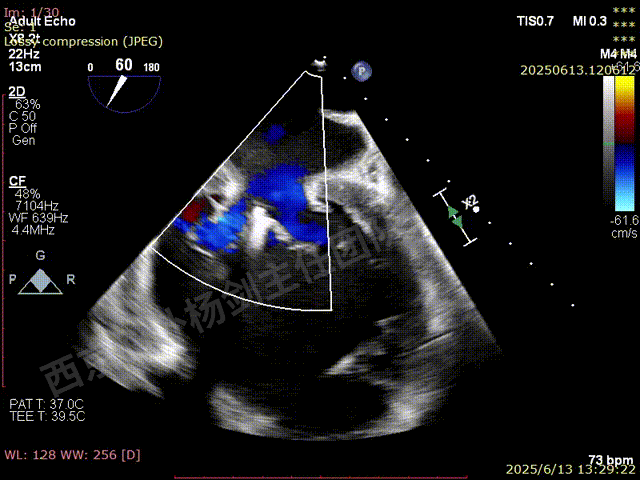

TAVR术后,全心增大,二尖瓣反流重度,三尖瓣反流重度。中量心包积液。左室严重增大,标准图像调整困难。主动脉瓣位带支架人工瓣膜瓣叶启闭正常,主动脉瓣位人工瓣上血流速度Vmax 148cm/s,PGmax 9mmHg,Vmean 86cm/s,PGmean 2mmHg, VTI 34.7cm,瓣周反流(轻)。估测肺动脉收缩压约49mmHg;左室收缩功能明显减低。LVEF:23%,EDV:364ml,ESV:221ml。

彩色血流示:二尖瓣反流缩流颈彩宽6.6mm,面积17cm²,容积30ml;二尖瓣瓣口面积6.6cm²,瓣环内径:左右径34mm,前后径34mm。2区瓣叶长度:前叶36mm,后叶20mm,叶环比1.6. 三尖反流面积17.2cm²,容积33ml,Vmax 291cm/s,PGmax 34mmHg。

二尖瓣后叶栓系严重,前叶相对错位,反流束沿2区分布广泛,2偏3区处存在反流。

反流宽度至少23mm,因影像调整困难,考虑实际反流更宽。